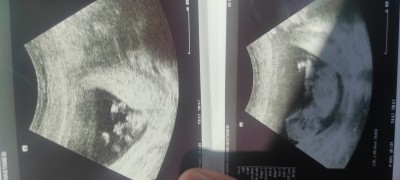

11 haftalikken doktor bebeyin kiza benziyor dedi 13 haftalik gittigimde bu sefer erkek dedi emin olamadim yardimci olursaniz cok seviniriimage

Gebelik haftası 17